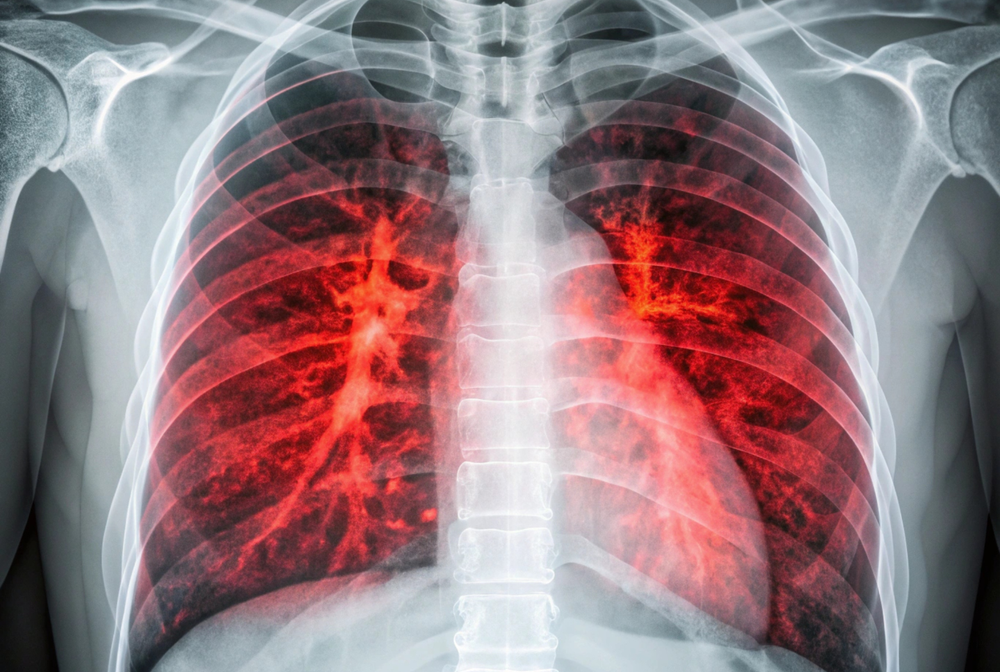

Healthy lungs contain millions of alveoli, tiny air sacs clustered like grapes at the ends of your smallest airways. These delicate structures have walls just one cell thick. Oxygen passes through these walls into surrounding blood vessels. Carbon dioxide moves in the opposite direction to be exhaled.

Emphysema destroys the walls between alveoli. Instead of millions of tiny, efficient air sacs, you develop fewer, larger spaces with much less surface area. The elastic tissue that helps lungs spring back after you exhale gets damaged. Your lungs lose their ability to empty completely.

The result is trapped air. Old air that should have been exhaled stays in your lungs, leaving less room for fresh oxygen-rich air to enter. Your breathing becomes shallow and rapid. You feel constantly short of breath. Simple activities like walking across a room leave you gasping.

The damage is irreversible. Once alveolar walls are destroyed, they cannot be repaired or replaced. This makes protecting your remaining lung tissue absolutely critical. Every bit of function you preserve matters enormously for maintaining independence and quality of life.